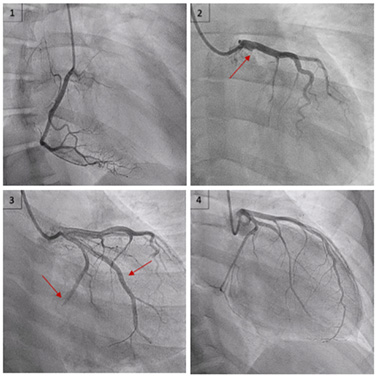

Devant des arguments forts pour un tableau de syndrome coronarien aigu, une coronarographie est réalisée.

Cette dernière retrouve une lésion monotronculaire sur occlusion aiguë de l'artère circonflexe proximale d'allure thrombotique (image 1 et 2).

Une thrombectomie productive permet un succès de revascularisation sans pose de stent (image 3). Il existe malheureusement une embolisation distale dans l'artère circonflexe et dans la première artère marginale (image 4).